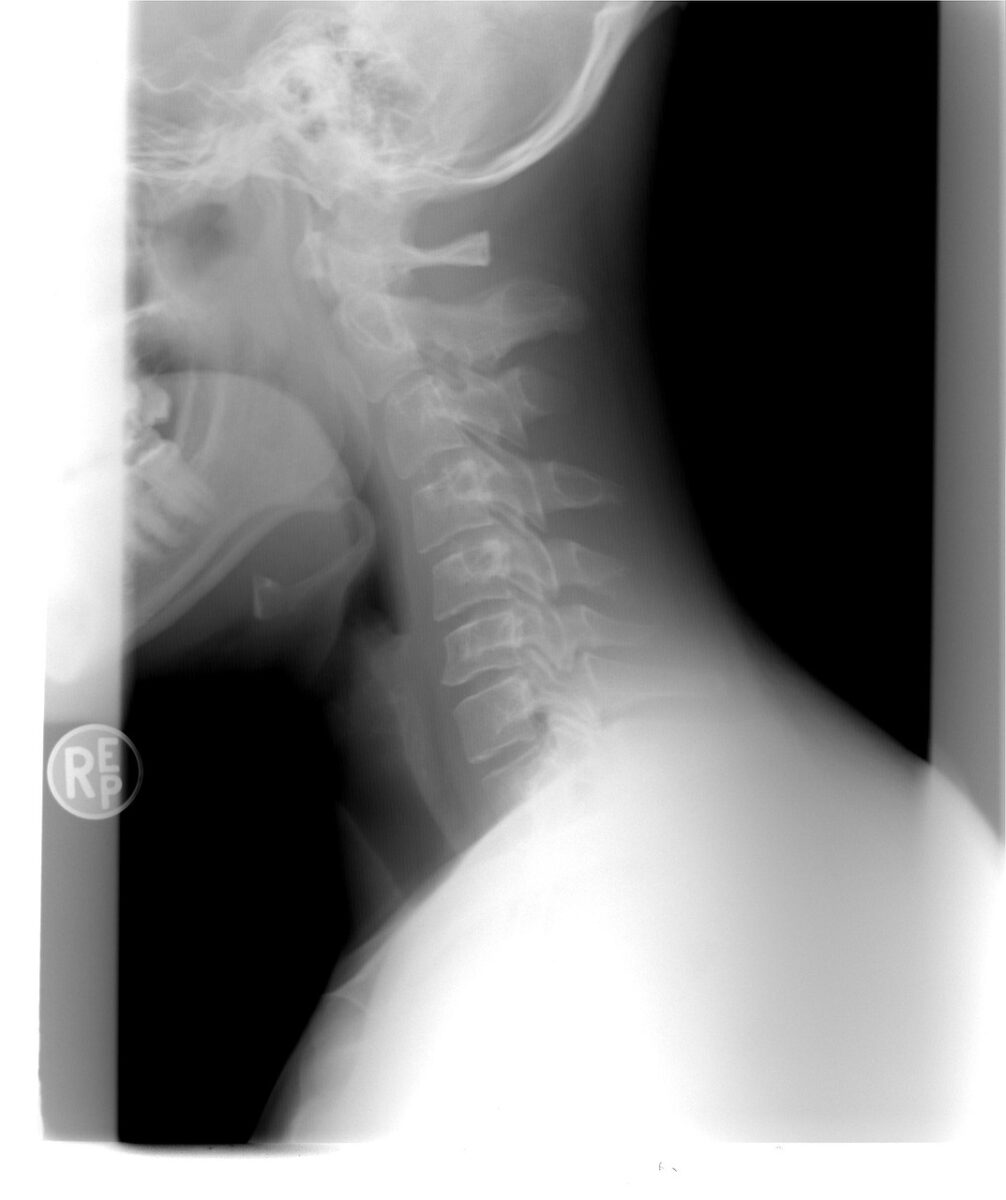

La cervicalgie désigne une douleur localisée au niveau des vertèbres cervicales, situées dans la partie supérieure de la colonne vertébrale. Cette douleur peut être aiguë, apparaissant brutalement après un faux mouvement ou un traumatisme, ou chronique, lorsqu’elle s’installe progressivement et dure plusieurs semaines.

Arthrose cervicale

Avec le temps, les articulations du cou peuvent s’user, entraînant de l’arthrose cervicale. Cette usure provoque des douleurs et une raideur du cou, souvent plus marquées le matin.

Hernie cervicale

La hernie discale cervicale survient lorsque l’un des disques intervertébraux se déplace et comprime un nerf. Cela provoque des douleurs irradiantes dans le bras et des engourdissements.